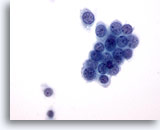

Figure 3

Breast FNA, Abscess.

Fine-needle aspirates of breast abscesses do not usually show epithelial cells. Cellular debris, lysed red cells and neutrophils are common features. 40x

Figure 3

Breast FNA, Abscess.

Fine-needle aspirates of breast abscesses do not usually show epithelial cells. Cellular debris, lysed red cells and neutrophils are common features.

40x